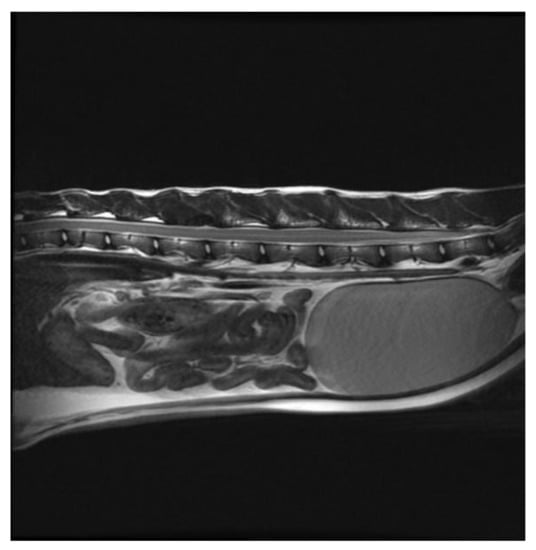

Successful Treatment of Vertebral Osteosarcoma in a Cat Using Marginal Surgical Excision and Chemotherapy

:1. Case Description

2. Materials and Methods

3. Results